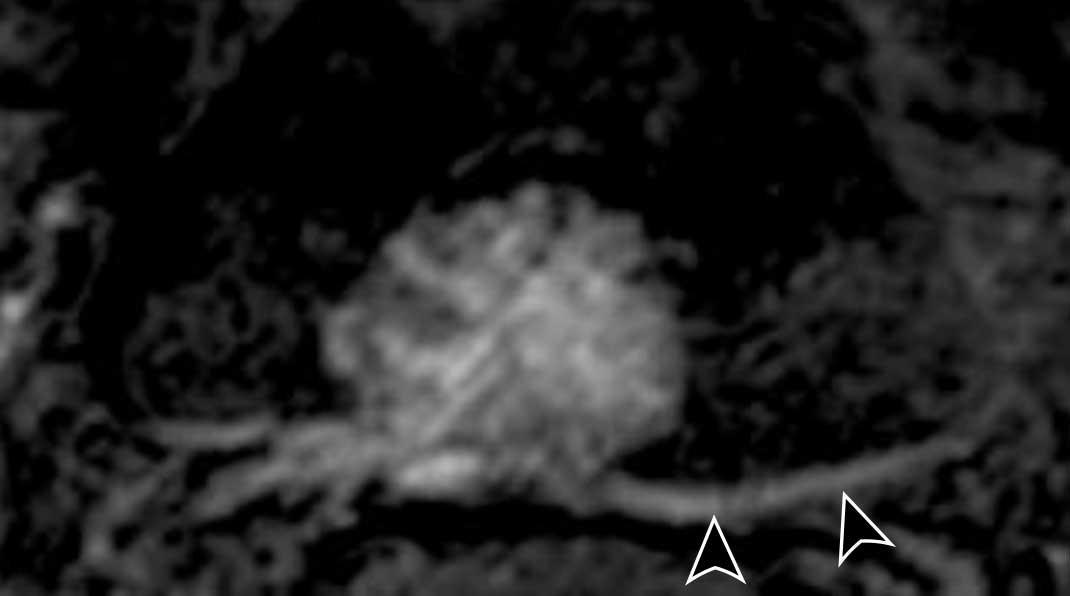

Dấu hiệu

- DCE: Ngấm thuốc sớm của lớp cơ được thấy rõ ràng trên chuỗi xung DCE.

Bản thân khối u nghèo mạch máu và không lan qua lớp cơ đang ngấm thuốc. - DWI/ADC: Có sự gián đoạn của cơ thành bàng quang, nhưng không có xâm lấn mỡ.

Kết luận

T2W 4/5, DCE 4 và DWI/ADC 4

Điểm VI-RADS cuối cùng: 4